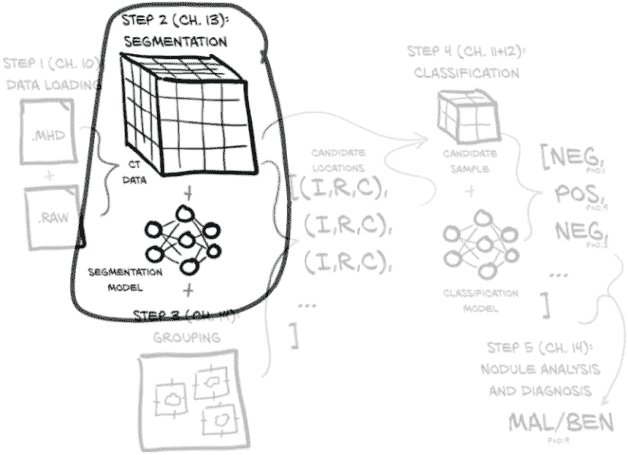

这意味着我们仍然专注于与第十一章相同的图 12.1 的同一部分。但现在我们正在努力使我们的分类模型工作良好而不是只是工作。本章重点讨论如何衡量、量化、表达,然后改进我们的模型执行工作的能力。

图 12.1 我们的端到端肺癌检测项目,重点放在本章的主题上:第 4 步,分类

13.1 向我们的项目添加第二个模型

在前两章中,我们完成了图 13.1 中显示的计划的第 4 步:分类。在本章中,我们不仅要回到上一步,而是回到上两步。我们需要找到一种方法告诉我们的分类器在哪里查找。为此,我们将对原始 CT 扫描进行处理,找出可能是结节的所有内容。这是图中突出显示的第 2 步。为了找到这些可能的结节,我们必须标记看起来可能是结节的体素,这个过程被称为分割。然后,在第十四章中,我们将处理第 3 步,并通过将这幅图像的分割掩模转换为位置注释来提供桥梁。

图 13.1 我们的端到端肺癌检测项目,重点关注本章主题:第 2 步,分割